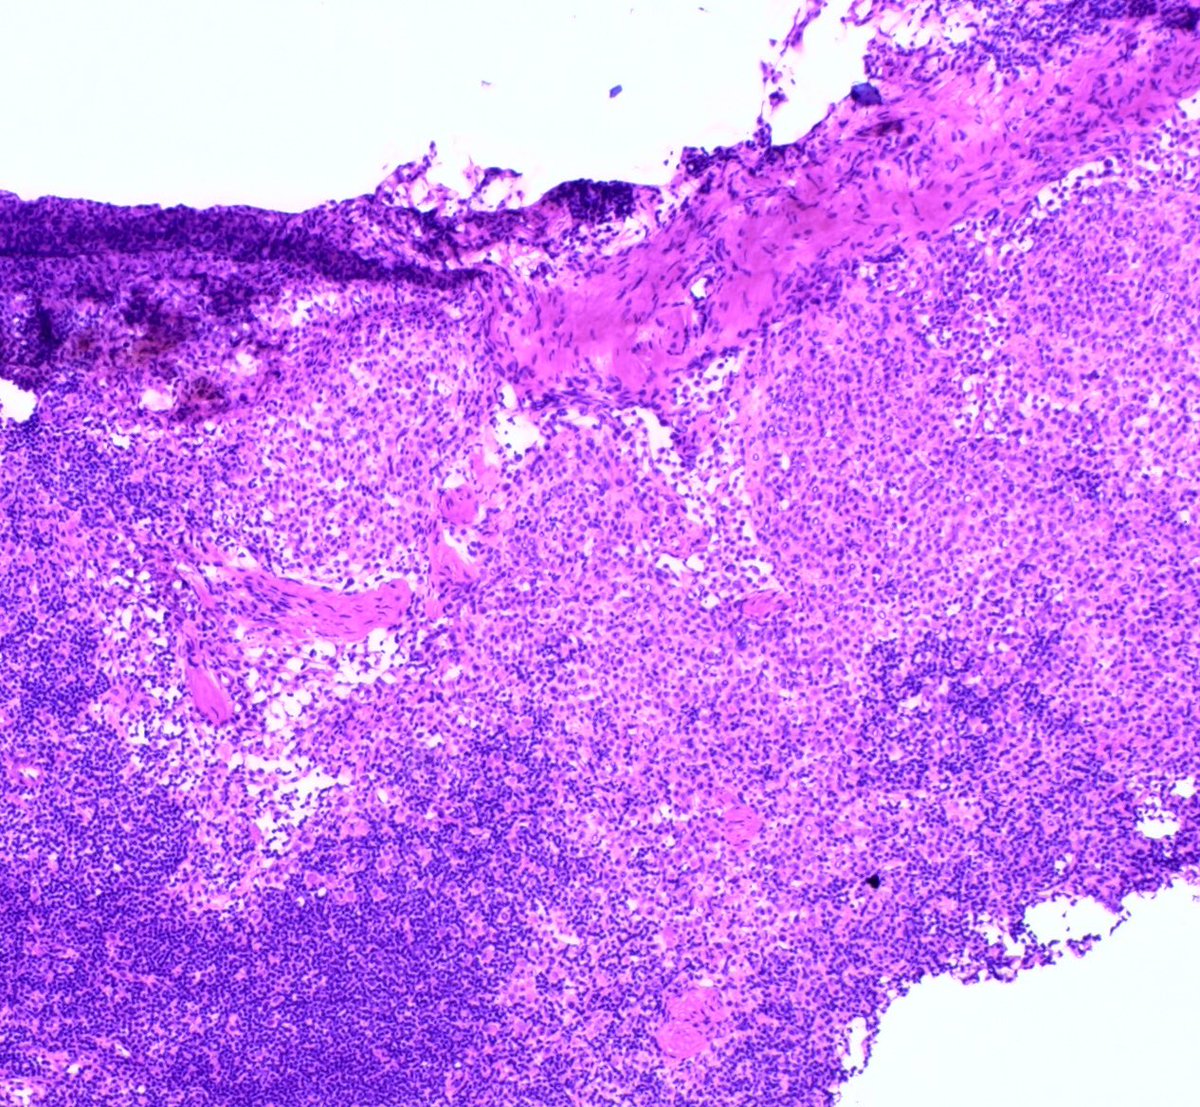

52 Year old female; multifocal right sided breast cancer undergoing mastectomy with SLN bx.

Intraoperative sentinel node touch prep shown. If cancer —> axillary dissection.